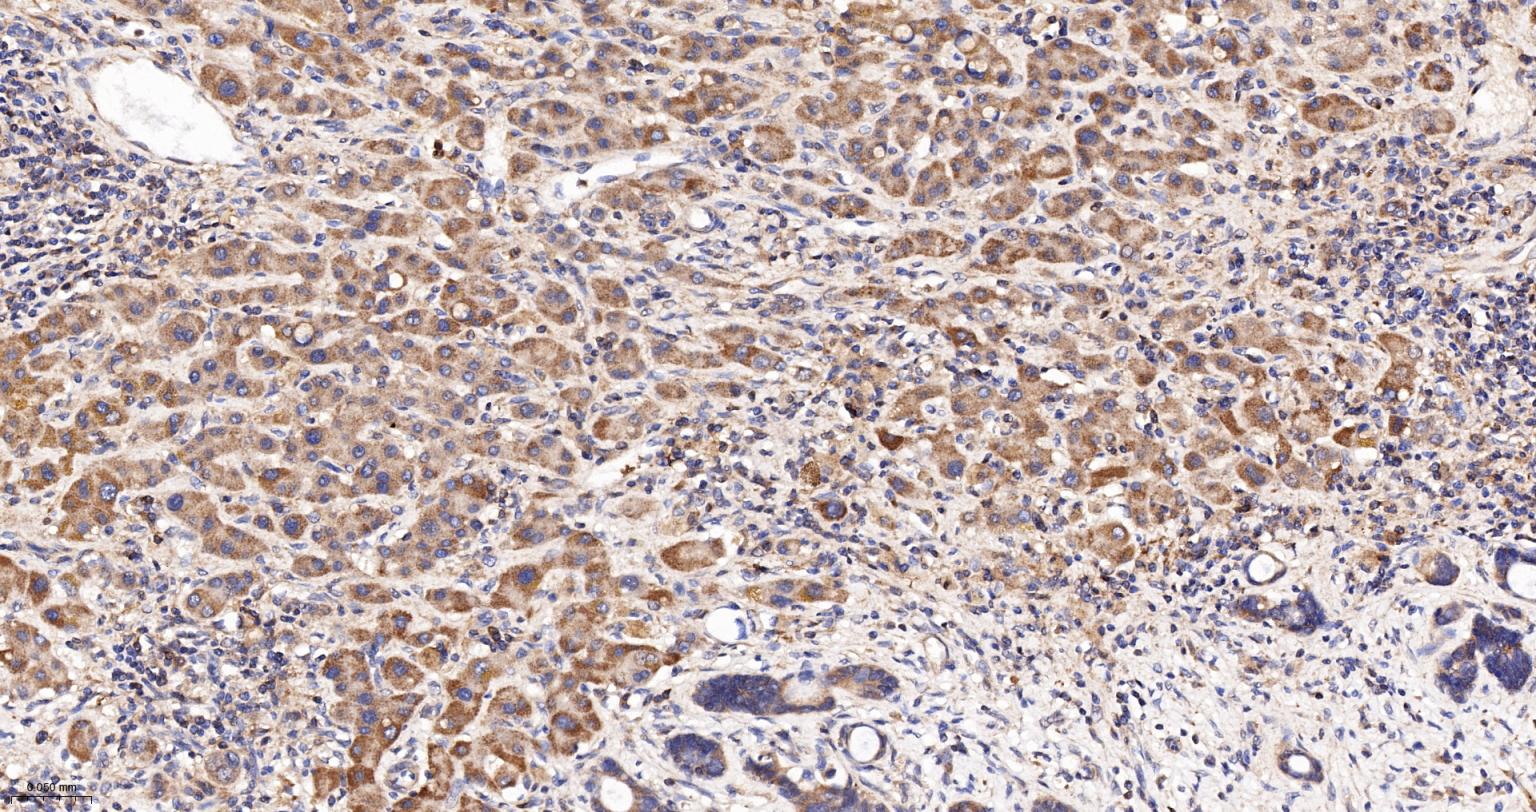

Paraformaldehyde-fixed, paraffin embedded Human Colon Cancer; Antigen retrieval by boiling in sodium citrate buffer (pH6.0) for 15 min; Antibody incubation with Cleaved-Caspase 3 p17 Monoclonal Antibody, Unconjugated(bsm-61090R) at 1:200 overnight at 4°C, followed by conjugation to the SP Kit (Rabbit, SP-0023) and DAB (C-0010) staining.